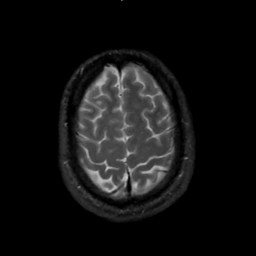

MR Study #1, February 10, 1991 -- Slice #42